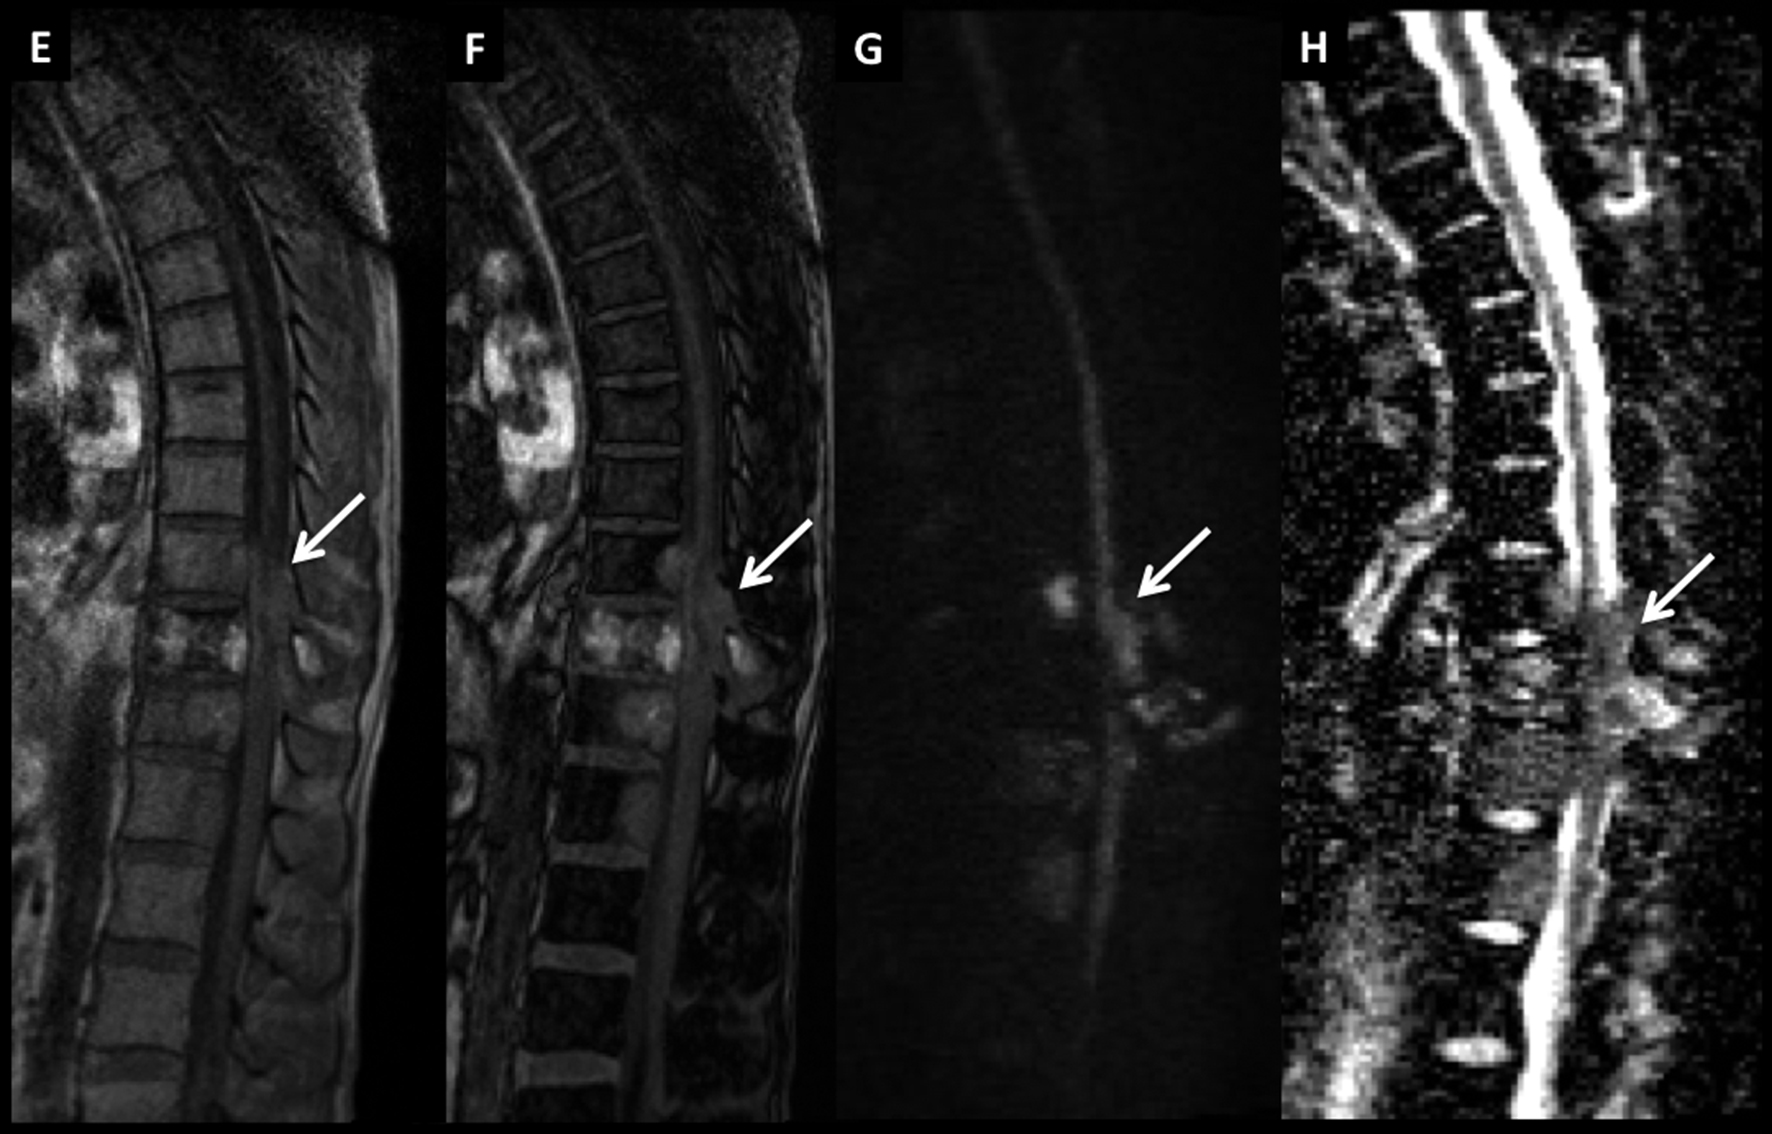

Figura 8

LNH, lesión medular, compromiso primario.

Paciente de 54 años con síndrome medular de instalación progresiva. En RM se identifica lesión medular cervical con ensanchamiento focal de varios segmentos, con alta intensidad de señal en secuencia T2 (A) y realce lineal, intenso, en secuencia T1 post-gadolinio (B).

LNH, lesión medular, compromiso primario. (cont)

En secuencia T2 en el plano axial (C) la alteración es heterogénea, centro-medular. Se decidió realizar biopsia de este proceso y el estudio histopatológico confirmó el diagnóstico de linfoma. Luego de la valoración sistémica no se evidenció compromiso asociado en otros territorios por lo que el diagnóstico final fue de LNH primario.